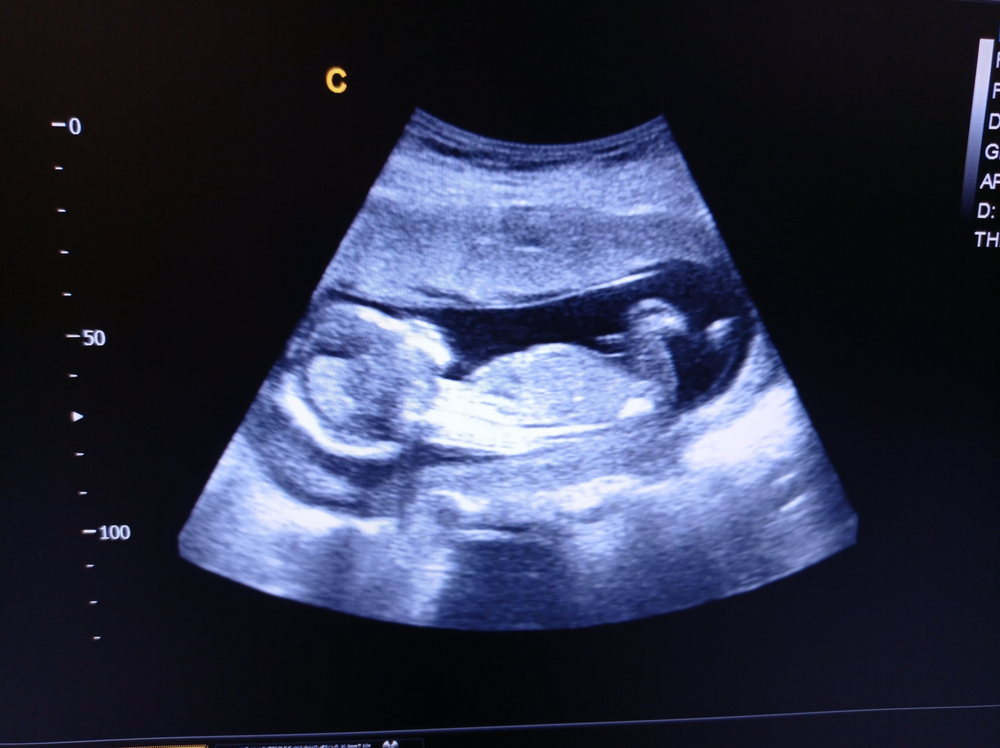

Melalui hasil USG janin 18 minggu, dokter bisa mengamati pertumbuhan Si Kecil dengan lebih jelas, mulai dari bentuk wajah, jari tangan dan kaki, hingga gerakan tubuh yang mulai aktif. Selain itu, USG ini juga bermanfaat untuk memastikan posisi plasenta, kondisi cairan ketuban, serta perkembangan organ dalam janin.

Pada hasil USG janin usia 18 minggu, dokter umumnya bisa mengamati beberapa hal berikut yang menandai perkembangan Si Kecil di dalam kandungan:

Di minggu ini, bentuk wajah Si Kecil, seperti hidung, bibir, dan kelopak mata, makin jelas terlihat. Jari-jari tangan dan kaki sudah terbentuk sempurna, bahkan kuku pun mulai tumbuh. Gerakan tangan dan kaki makin aktif dan bisa diamati, misalnya saat janin menendang atau memegang tali pusat.

Detak jantung janin di usia ini makin kuat dan bisa terdengar jelas, berkisar antara 120–160 kali per menit. Organ-organ penting, seperti otak, paru-paru, ginjal, hati, dan sistem pencernaan, juga terus berkembang dan bisa mulai diamati melalui monitor USG.

Jika posisi janin memungkinkan, organ kelamin biasanya sudah bisa terlihat cukup jelas, sehingga dokter bisa memperkirakan jenis kelamin janin. Namun, ketepatannya tergantung pada posisi janin dan kondisi saat pemeriksaan.